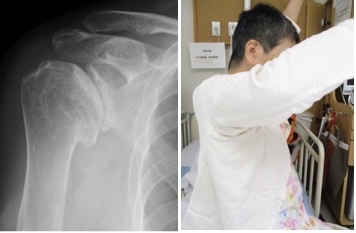

関節リウマチ患者に対する腱移行および手関節形成術

手関節の変形により腱断裂(特に伸筋腱)が生じ、急に指が伸びなくなる患者さんがいます。小指から始まり、比較的早期に手術をしない薬指中指と断裂が進行します。

断裂が進行しないように手関節の形成と、切れた腱に対しては直接縫合することは困難なため、隣接する正常な腱を用いて腱移行や腱移植を行ないます。

術前(写真)

術後(写真)

手術前の指の伸展不足が改善しています